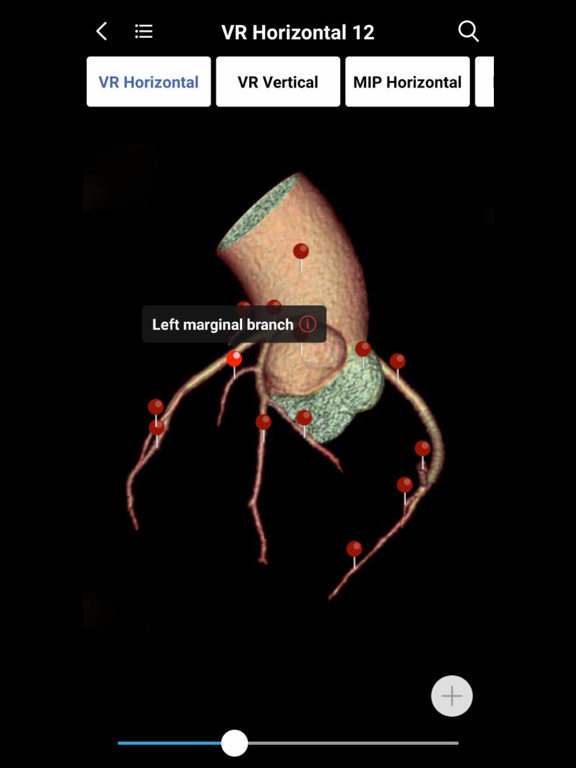

1. Normal imaging anatomy atlases which have the detailed structure labeling in coronal, sagittal, axis section. You can search any imaging structures conveniently at any time. Currently all imaging atlases’ images are JEPG format,  and they will be replaced by DICOM images very soon. This means you can to adjust the window width and window location of all images in the atlases. It's unbelievable!

2. MedImaging also includes 3D AR and 2D  anatomy pictures. When you slide to any image in the atlas, you can easily find the 3D and 2D anatomical pictures most relevant to the image. This means that you don't have to go through the anatomy textbooks if you forget the association between the general body anatomy and imaging anatomy. Just one click, you can build the intrinsic association between general anatomy and medical imaging. You'll understand medical imaging more efficiently and easily.

3. Clinically 2D diagrams are also integrated seamlessly into all images in the atlases. For example, cerebrovascular blood supply area, DSA vascular segmentation, cerebral leaf segmentation, liver segmentation, pulmonary leaf segmentation, etc.